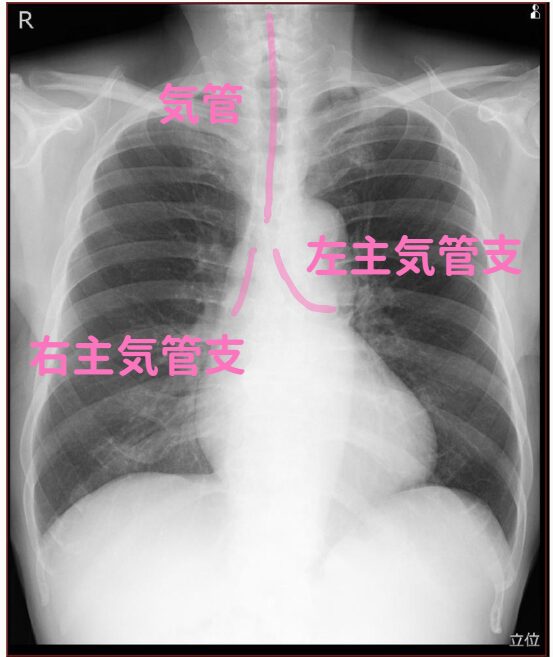

(7)気管・左右主気管支

左右の主気管支の角度が違うのは有名ですよね。

この角度の差が、誤嚥性肺炎が右に多い理由だと考えています。